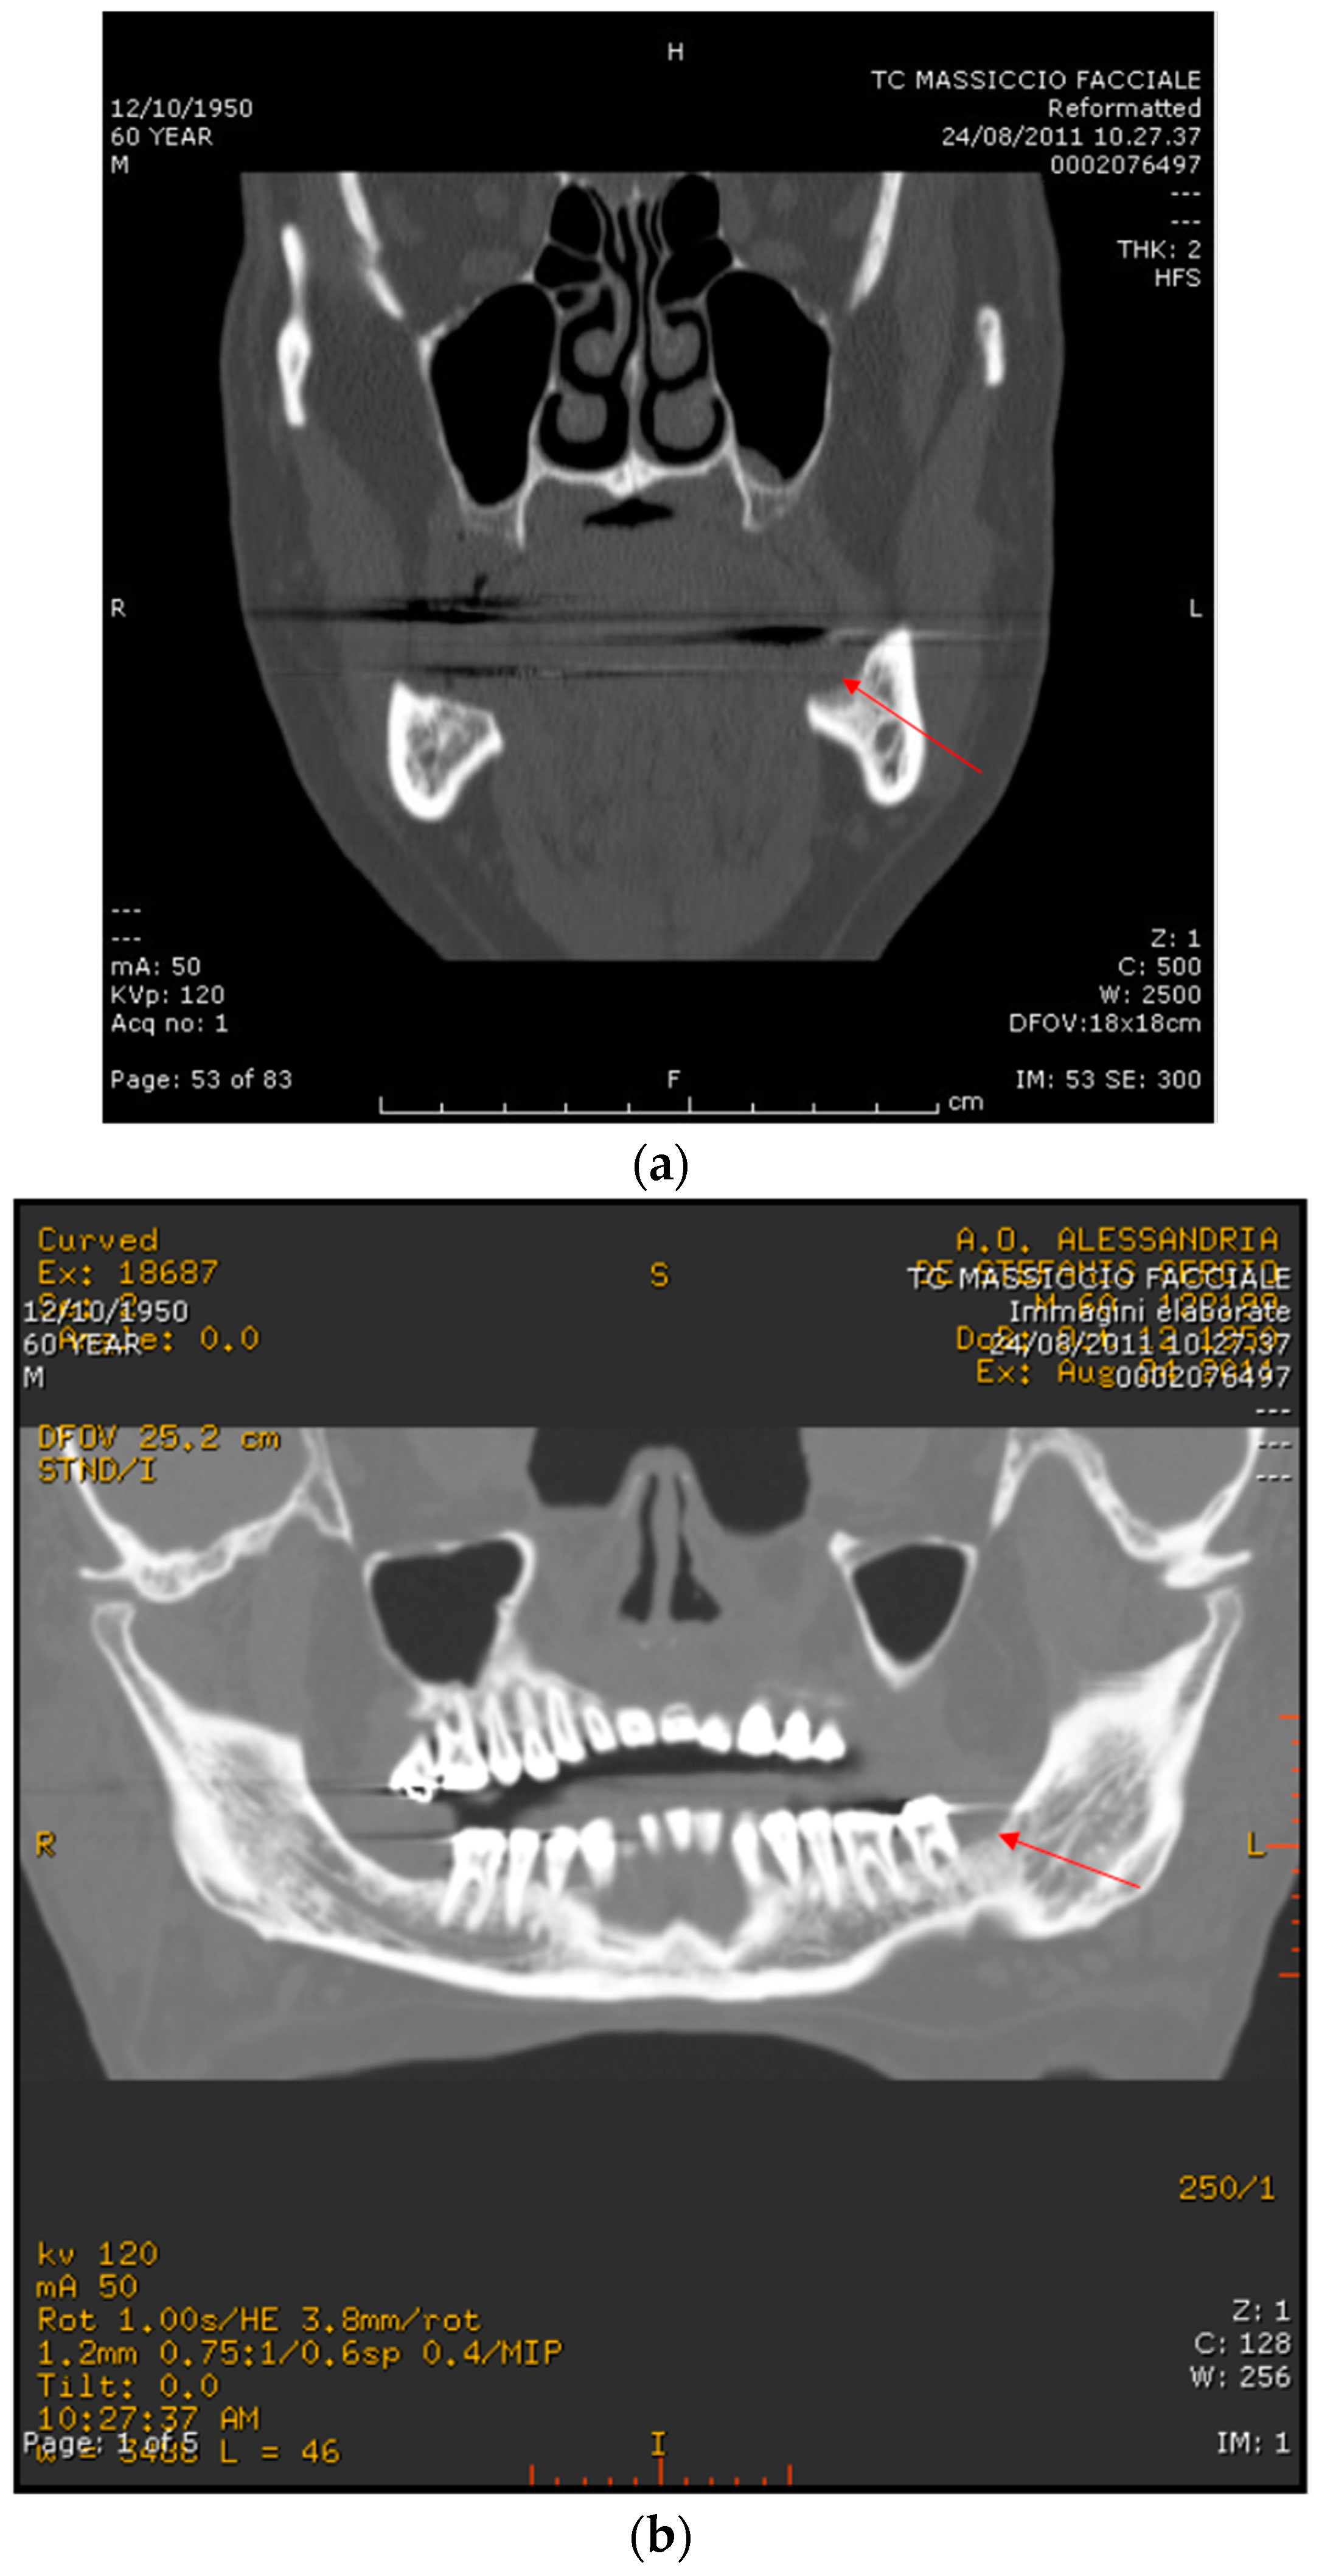

2.1. Case Report 1

2.2. Case Report 2